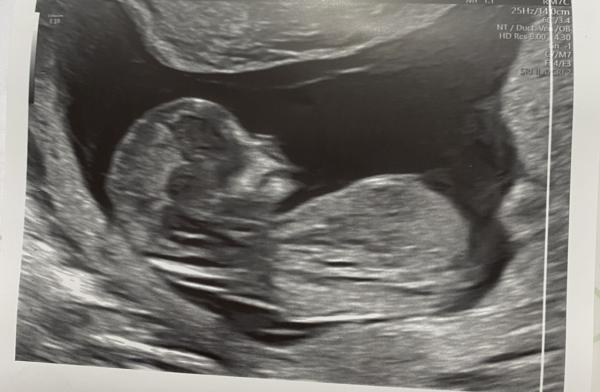

Hey ihr, Ich hatte gestern mein ETS bei 13+1. Kennt sich jemand mit der Nub Theorie aus und kann eine Tendenz fürs Geschlecht abgeben? Ich würde mich total über eure Meinung freuen.

ich finde, man kann den Nub (Knubbel) auf diesen US-Bildern nicht gut genug erkennen, um einen Winkel bestimmen zu können. Aber auch bei optimalem Bild ist es für Laien fast nicht möglich, die Nub-Theorie anzuwenden, denn dafür braucht man sehr viel Erfahrung, und die hat keiner von uns, sondern nur ein Gynäkologe.

Die Nub-Methode funktioniert daher nur zuverlässig, wenn sie von Experten angewandt wird. Wenn wir als Laien rätseln, ist die Trefferquote bei 50 Prozent.

Du wirst dich also noch ein paar Wochen gedulden müssen, bis man im Ultraschall Eindeutiges sieht. Oder du machst einen NIPT- oder Harmony-Test, auch hier wird das Geschlecht sicher bestimmt.